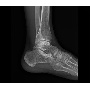

Klinikai esetek

Klinikai esetek 2.

Klinikai esetek 3.

Klinikai esetek 4.